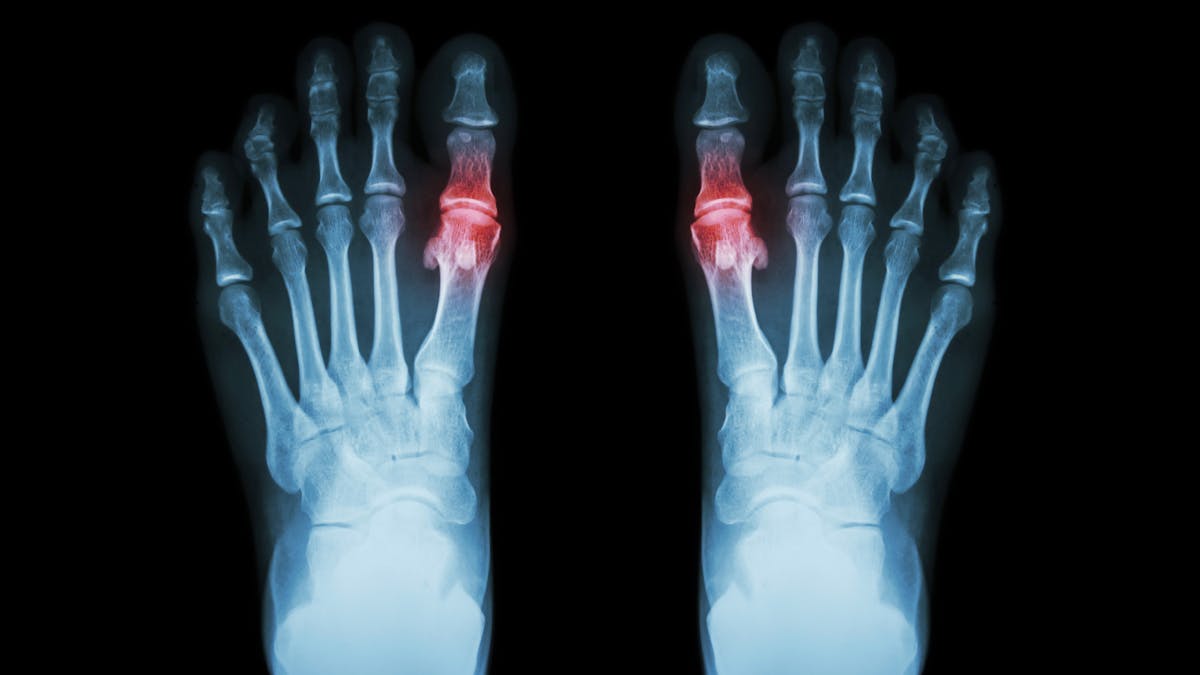

Can we blame gout’s resurgence on ketosis? I don’t call this a diet, but a new beginning

| Caries/Crooked teeth (3) | Gout (4) | Success story (190) |